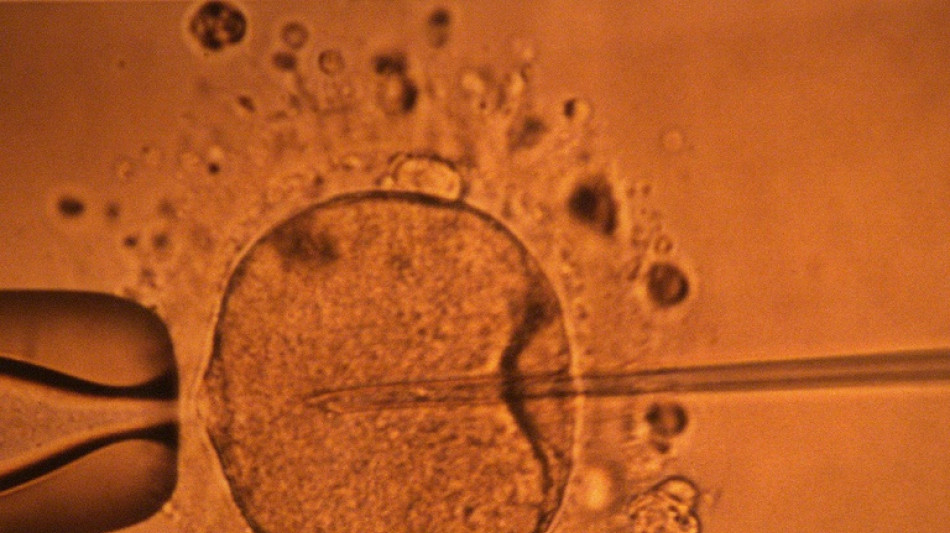

Un estudio apoya hipótesis de disminución mundial de concentración de espermatozoides

La concentración de espermatozoides, uno de los factores de la fertilidad masculina, disminuyó significativamente en todo el planeta en las últimas décadas, según un estudio publicado el martes.

"La concentración de espermatozoides disminuyó significativamente entre 1973 y 2018", resumen los autores de este trabajo publicado en la revista Human Reproduction Update y realizado mediante la compilación de unos 40 estudios previos.